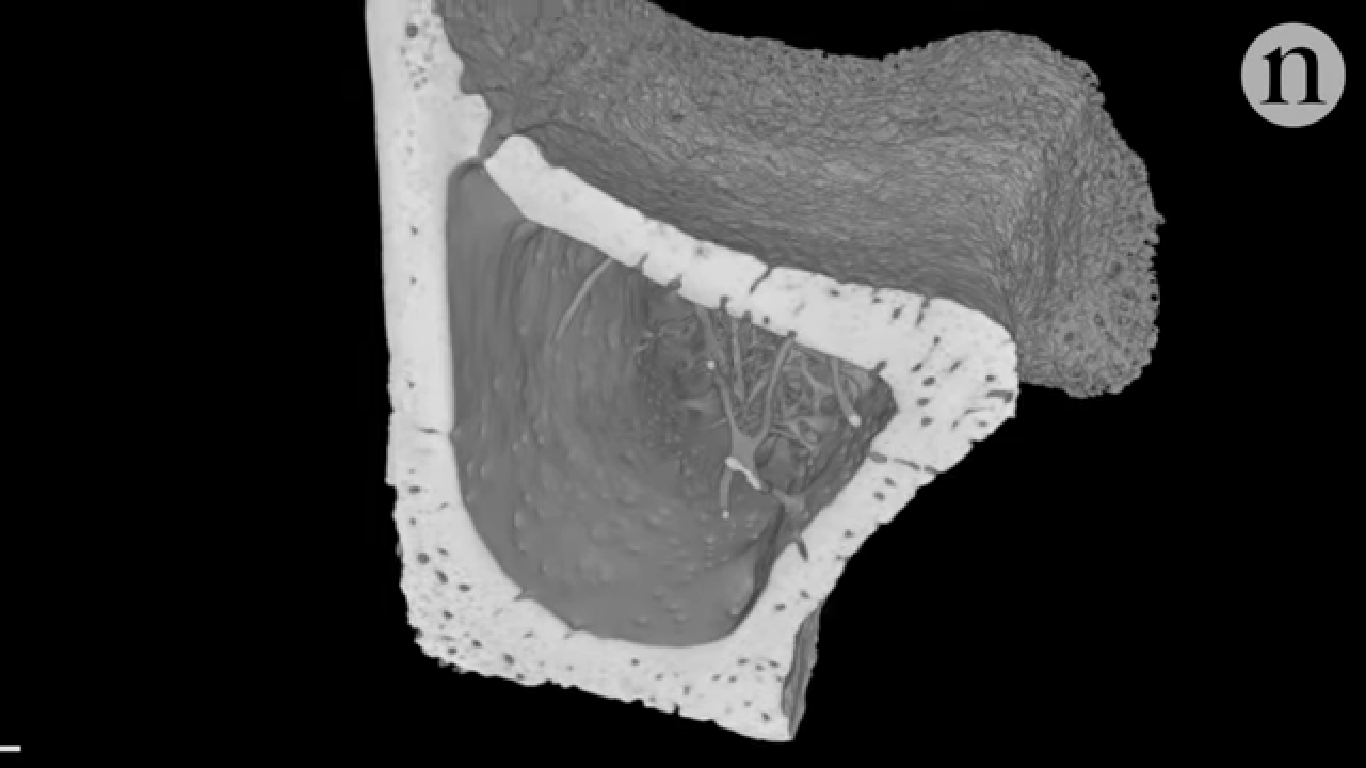

ภาพของหลอดเลือดชนิดใหม่ ซึ่งจะสังเกตได้ว่าในกระดูกที่โปร่งใสของหนูมีเส้นกระจายออกมาอยู่